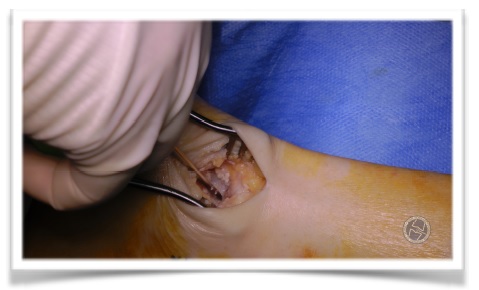

Primer paso quirúrgico:

Incisión para aquilea lateral y profundización hasta ladisección del os trigonum; resección del mismo, que

no pudo realizarse completamente sino por fragmentos.